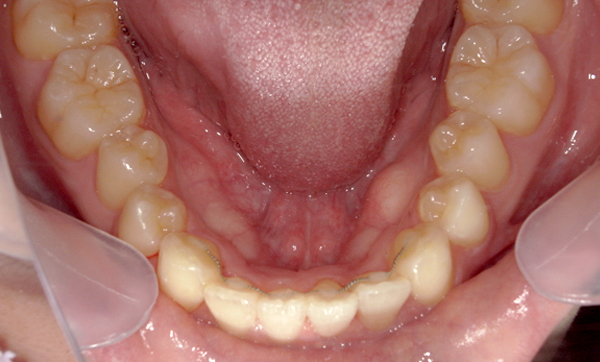

症例_008 「上下の前歯」症例

治療期間:13ヶ月金額:57万円+税40代女性捻転歯前歯のガタガタ

Before | After |